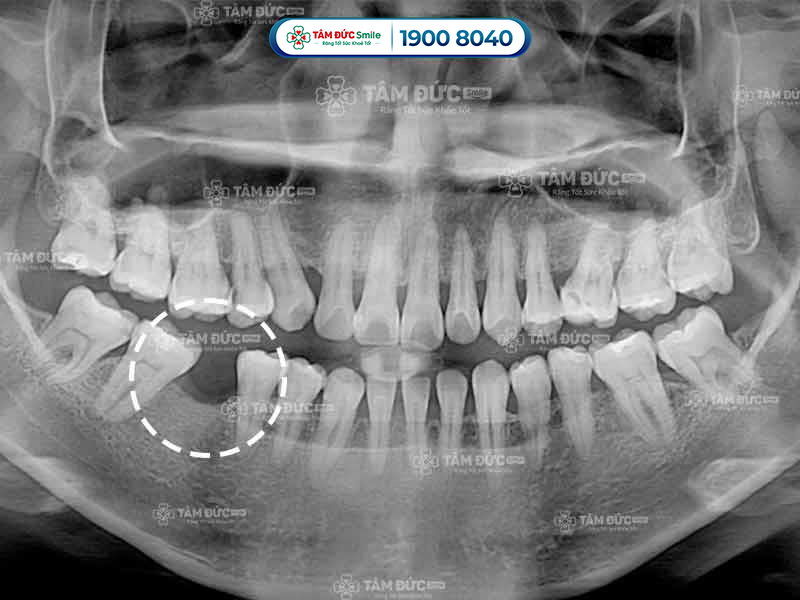

10.2. Bước 2 - Chụp phim CT Cone Beam và làm các xét nghiệm

Ngoài chụp phim CT, Quý khách còn được làm 1 số xét nghiệm cần thiết để đánh giá sức khỏe có đủ điều kiện trồng răng Implant hay không. Khi có đủ các kết quả kiểm tra, bác sĩ bắt đầu xây dựng phác đồ điều trị phù hợp.

10.8. Bước 8 - Chụp CT tái khám sau khi cắm Implant

Kết quả chụp CT tái khám sau khi trồng răng Implant giúp bác sĩ xác định hiệu quả của kết quả phục hình. Sau đó, bác sĩ sẽ hướng dẫn Quý khách cách chăm sóc răng Implant hiệu quả.

- Kiểm tra chất lượng xương hàm trước khi trồng răng bằng cách chụp phim CT.

Trụ Implant kém chất lượng sẽ nhanh chóng bị cơ thể đào thải ra ngoài, làm Quý khách bị chảy máu chân răng hoặc viêm nướu. Kết quả chụp phim X-Quang cho thấy xương không bám vào trụ Implant, lúc này Quý khách cần phải trồng răng lại từ đầu.